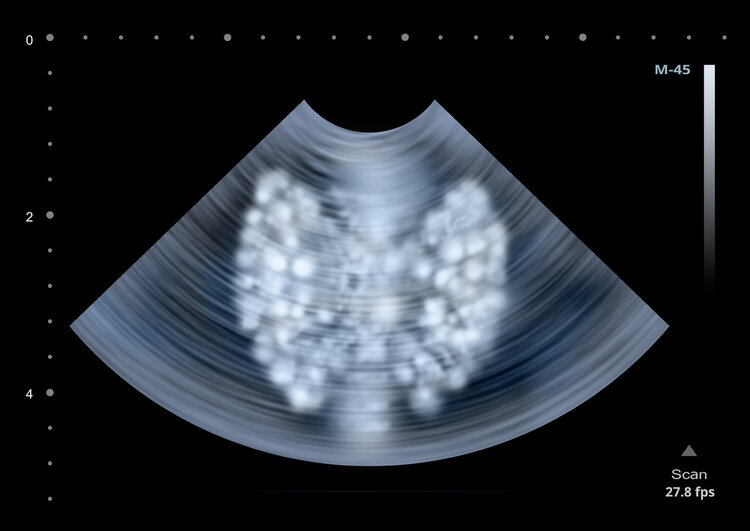

单靠触摸和肉眼无法准确判断结节良恶性,想要区分甲状腺结节的良恶性,首选甲状腺的超声检查,可以大致确定甲状腺结节的数量、大小、位置、形状、质地、钙化、血供等,评估颈部有无淋巴结,淋巴结的大小、结构特点等,还可以看到结节的外观,区分甲状腺结节的性质。

一般来说,良性的甲状腺结节,表面光滑且活动性好,用手触摸时可以活动;如果是恶性结节,在B超上有低回声,且形态不规则不清晰、微钙化等异常特征。